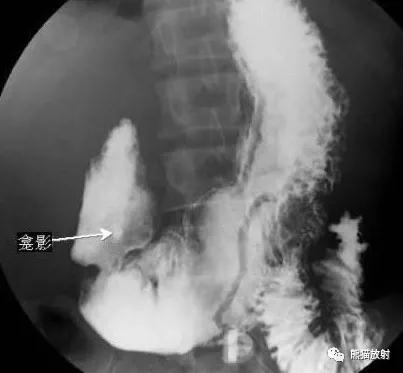

①憩室充盈后显示向肠腔外突出的圆形、椭圆形或烧瓶形的囊状阴影,轮廓光滑、大小不一,憩室充满后多能收缩排空。

左图上箭头示十二指肠降段内侧小憩室,憩室颈部狭窄,内见气液平面

右图右箭头示意憩室周围肠黏膜皱襞增粗,排空延长,提示憩室炎症

钡餐造影示:十二指肠第二、三段两个向腔外突出的憩室